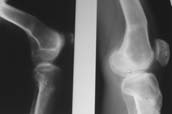

К сожалению, подобное осложнение "нет-нет да и возникает" при удлинении, коррекции деформации голени. В англоязычной литературе оно описано как "patella baja". Один из вариантов лечения - проксимальное перемещение надколенника приемами чрескостного остеосинтеза.